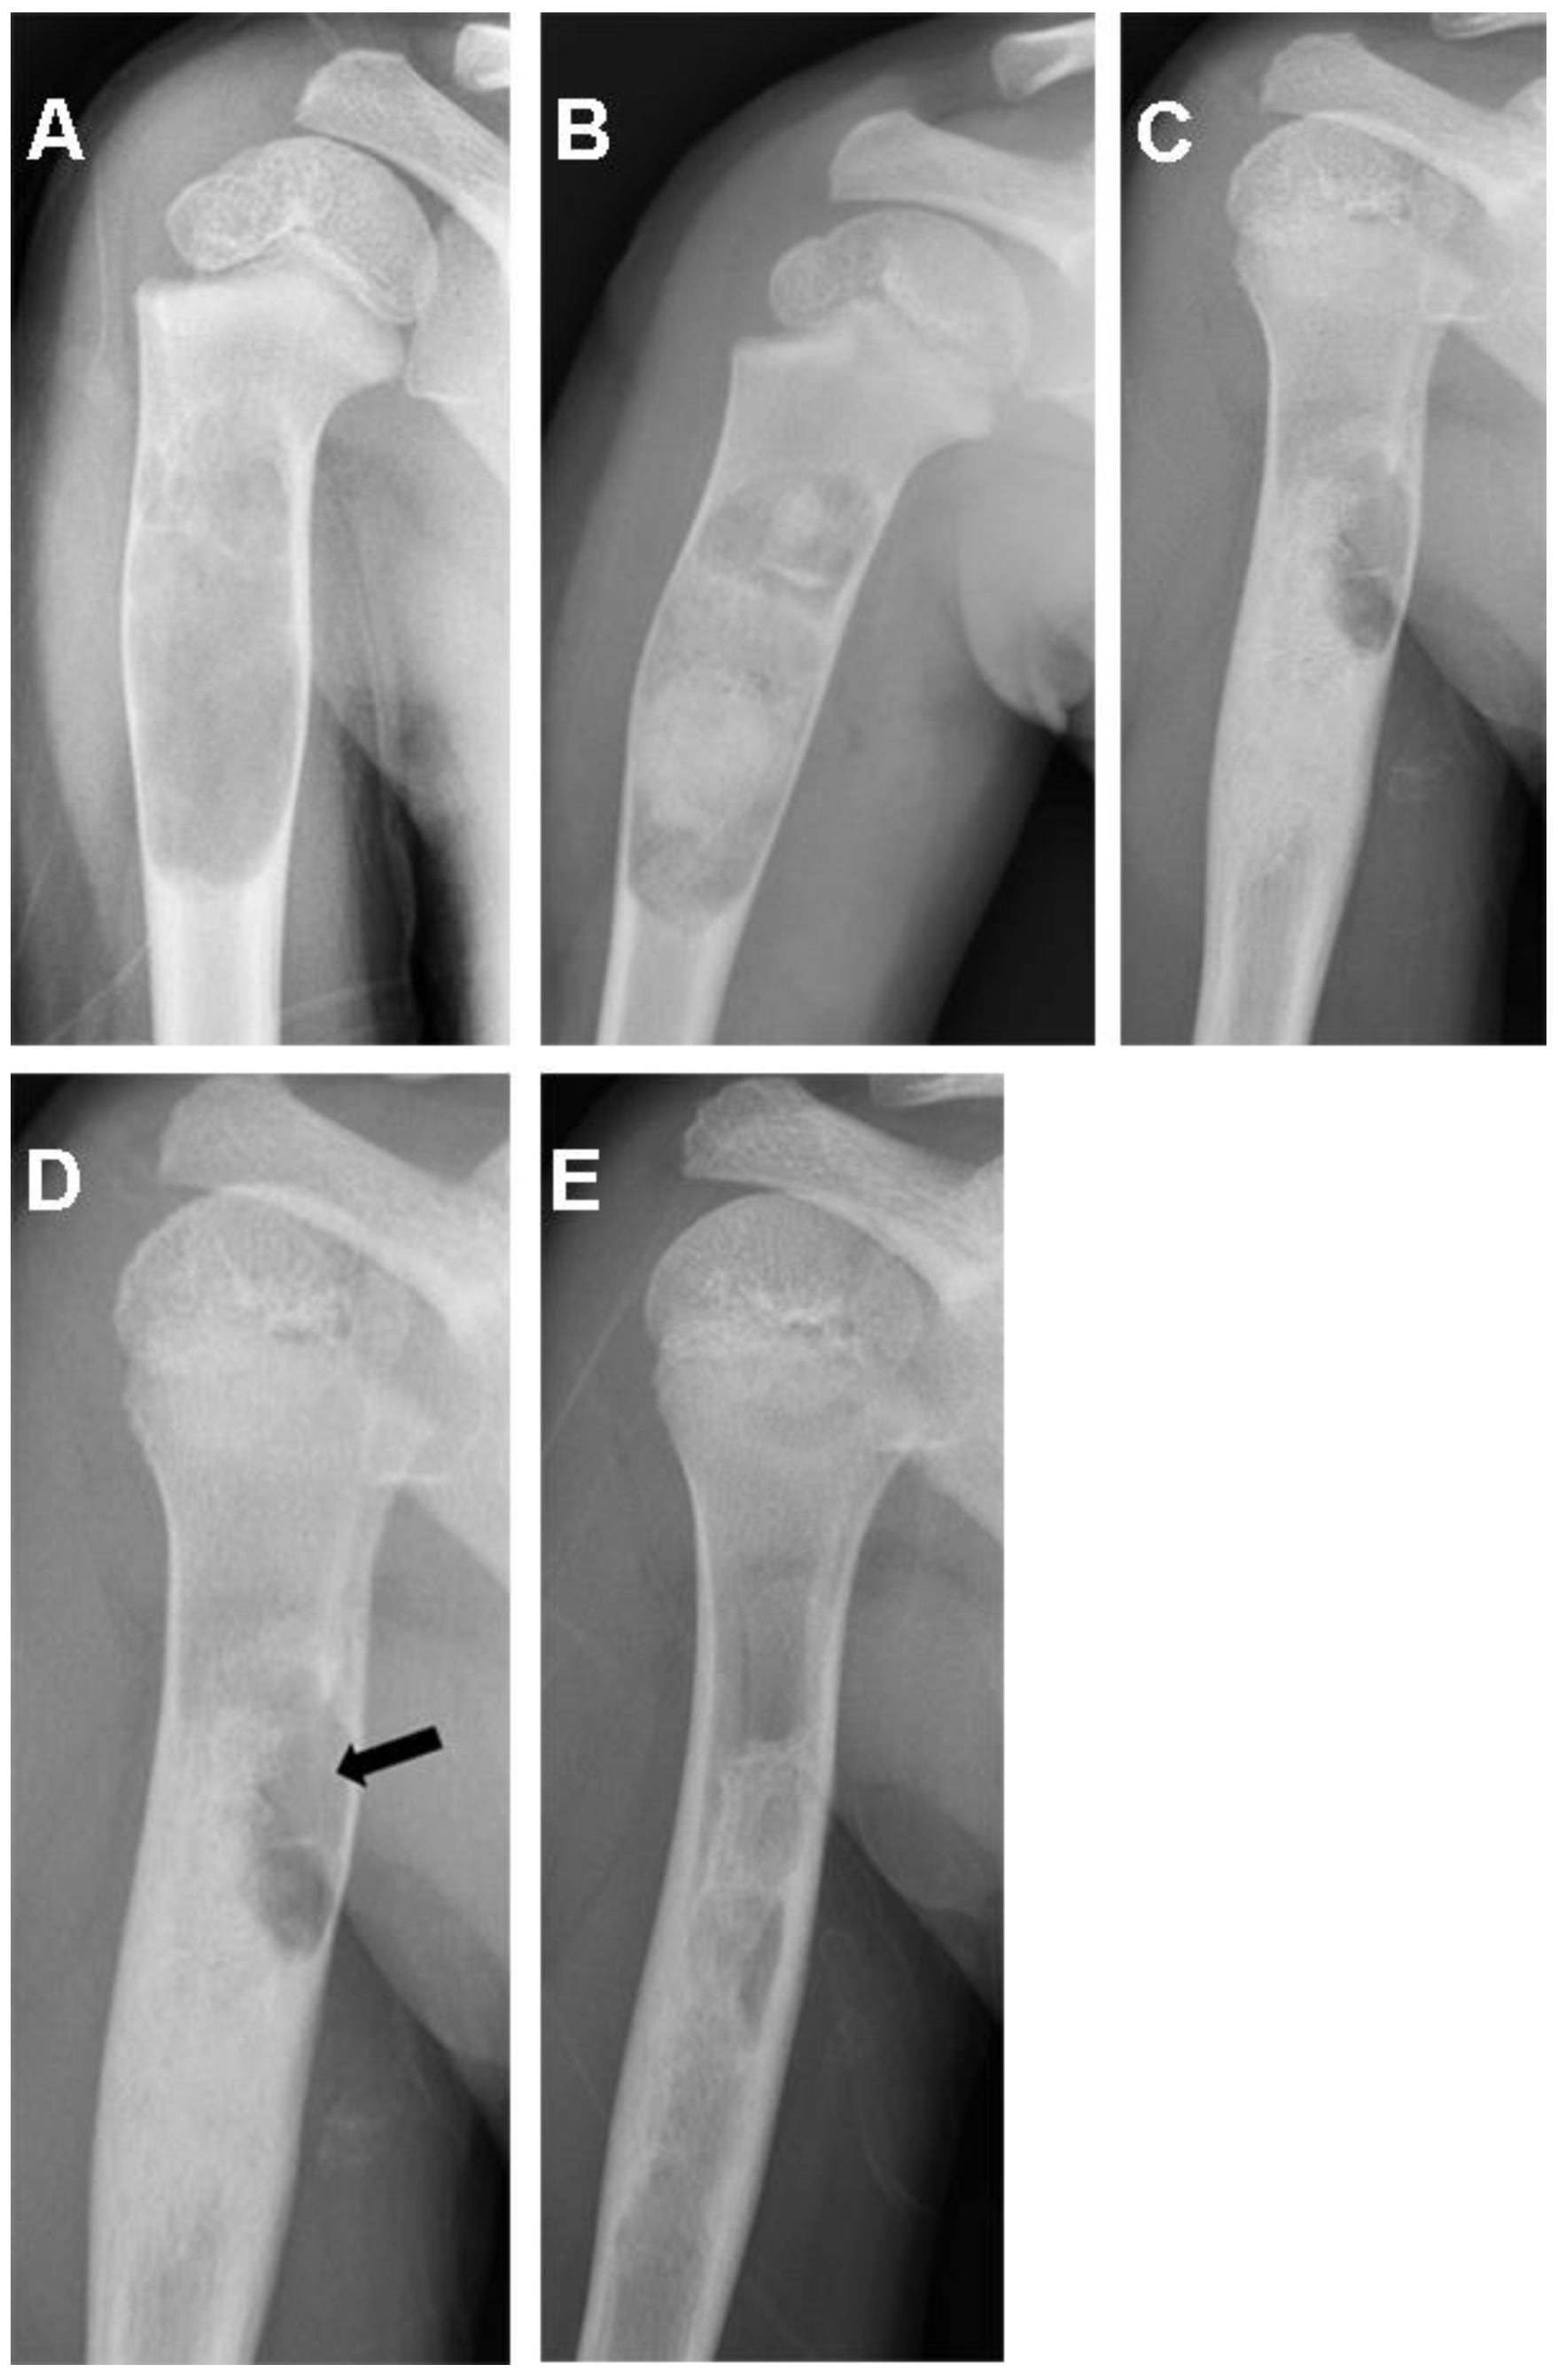

| 15/F/9 | Humerus | Simple bone cyst | 70.2 |